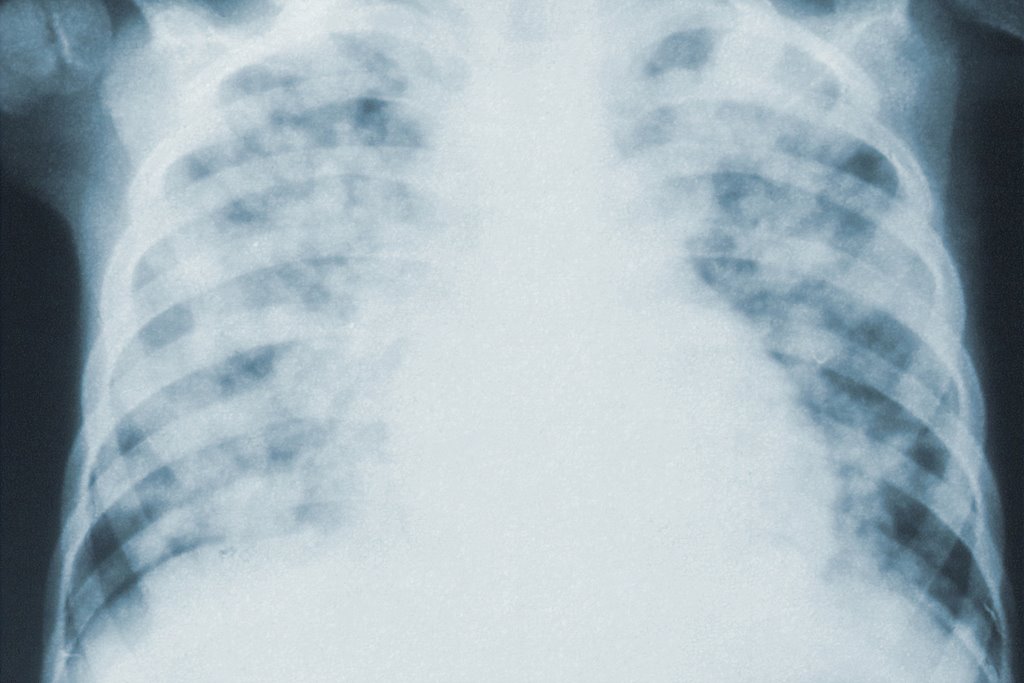

대표적인 호흡기 질환인 폐렴은 세균, 바이러스, 곰팡이에 의해서 발생하며, 원인균에 따라 세균성 폐렴, 바이러스성 폐렴, 진균성 폐렴으로 분류합니다.

폐렴은 면역력과 저항력이 약한 어린이나 노인의 경우 생명을 위협할 수도 있으므로 결코 가볍게 넘겨서는 안 됩니다.